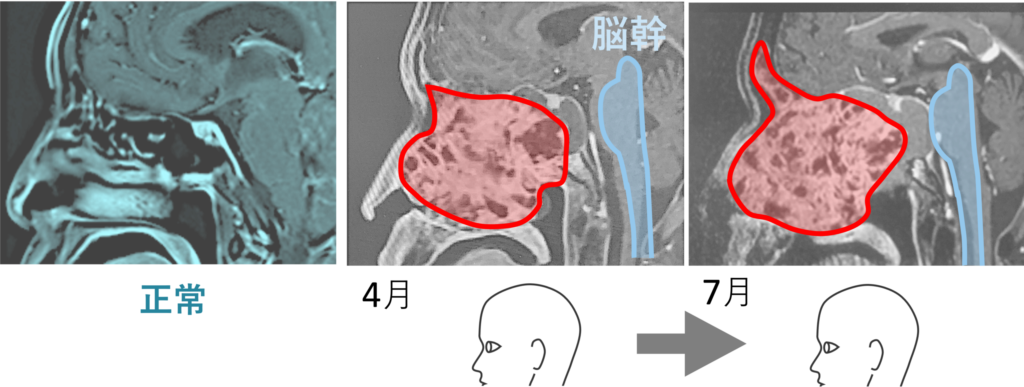

頭部のガンである。巨大化しており、脳幹に肉薄している。脳幹が侵されると、ここは呼吸や心拍の中枢ゆえに死に至る。 “死の宣告” はそれを踏まえたものである。

前年10月の画像を見ると、ガンの向かって左 (鼻のあたり) に空洞があることが分かる。まだガンが大きくなるスペースは残されていた。ところが1月の画像をみるとその空洞はなくなっている。もうガンが大きくなるスペースがなくなり、すし詰め状態となっている。こうなると、やがて脳幹 (画像の青色でなぞった部分) をガンが襲うことになる。これは死を意味する。後述するが、ドクターが予測した その時“” は、3月中であった。10月から1月にかけての巨大化の速度から、この調子で行くと3月に脳幹に達すると推測したのだ。

1月から4月にかけてやや大きくなったかに見えたのは気のせいではなかった。明らかにガンは大きくなっている。その証拠が、耳が聞こえなくなり、左顔面が痺れ、ついで目が見えづらくくなったという現象である。

3月に倒れると宣告を受けた。しかし生きている。すなわち、脳幹 (青で塗りつぶした部分) には近づかず、逆方向の鼻孔や額部に張り出してきていることが画像から分かるのである。ガンがふやけてきた (軟化してきた) から大きくなってきているのであり、大きくなることは必要なのであるが、命の根幹である脳幹を避けるようにして大きくなっているのである。生き続けようとする生命は、こういうことをやってくる。都合のいいように、柔軟にかわしたり変化したりする。決して偶然ではないのである。そういう「印象」を僕は持つのである。それは下リンクのような奇跡を経験してきたからそう思うのである。